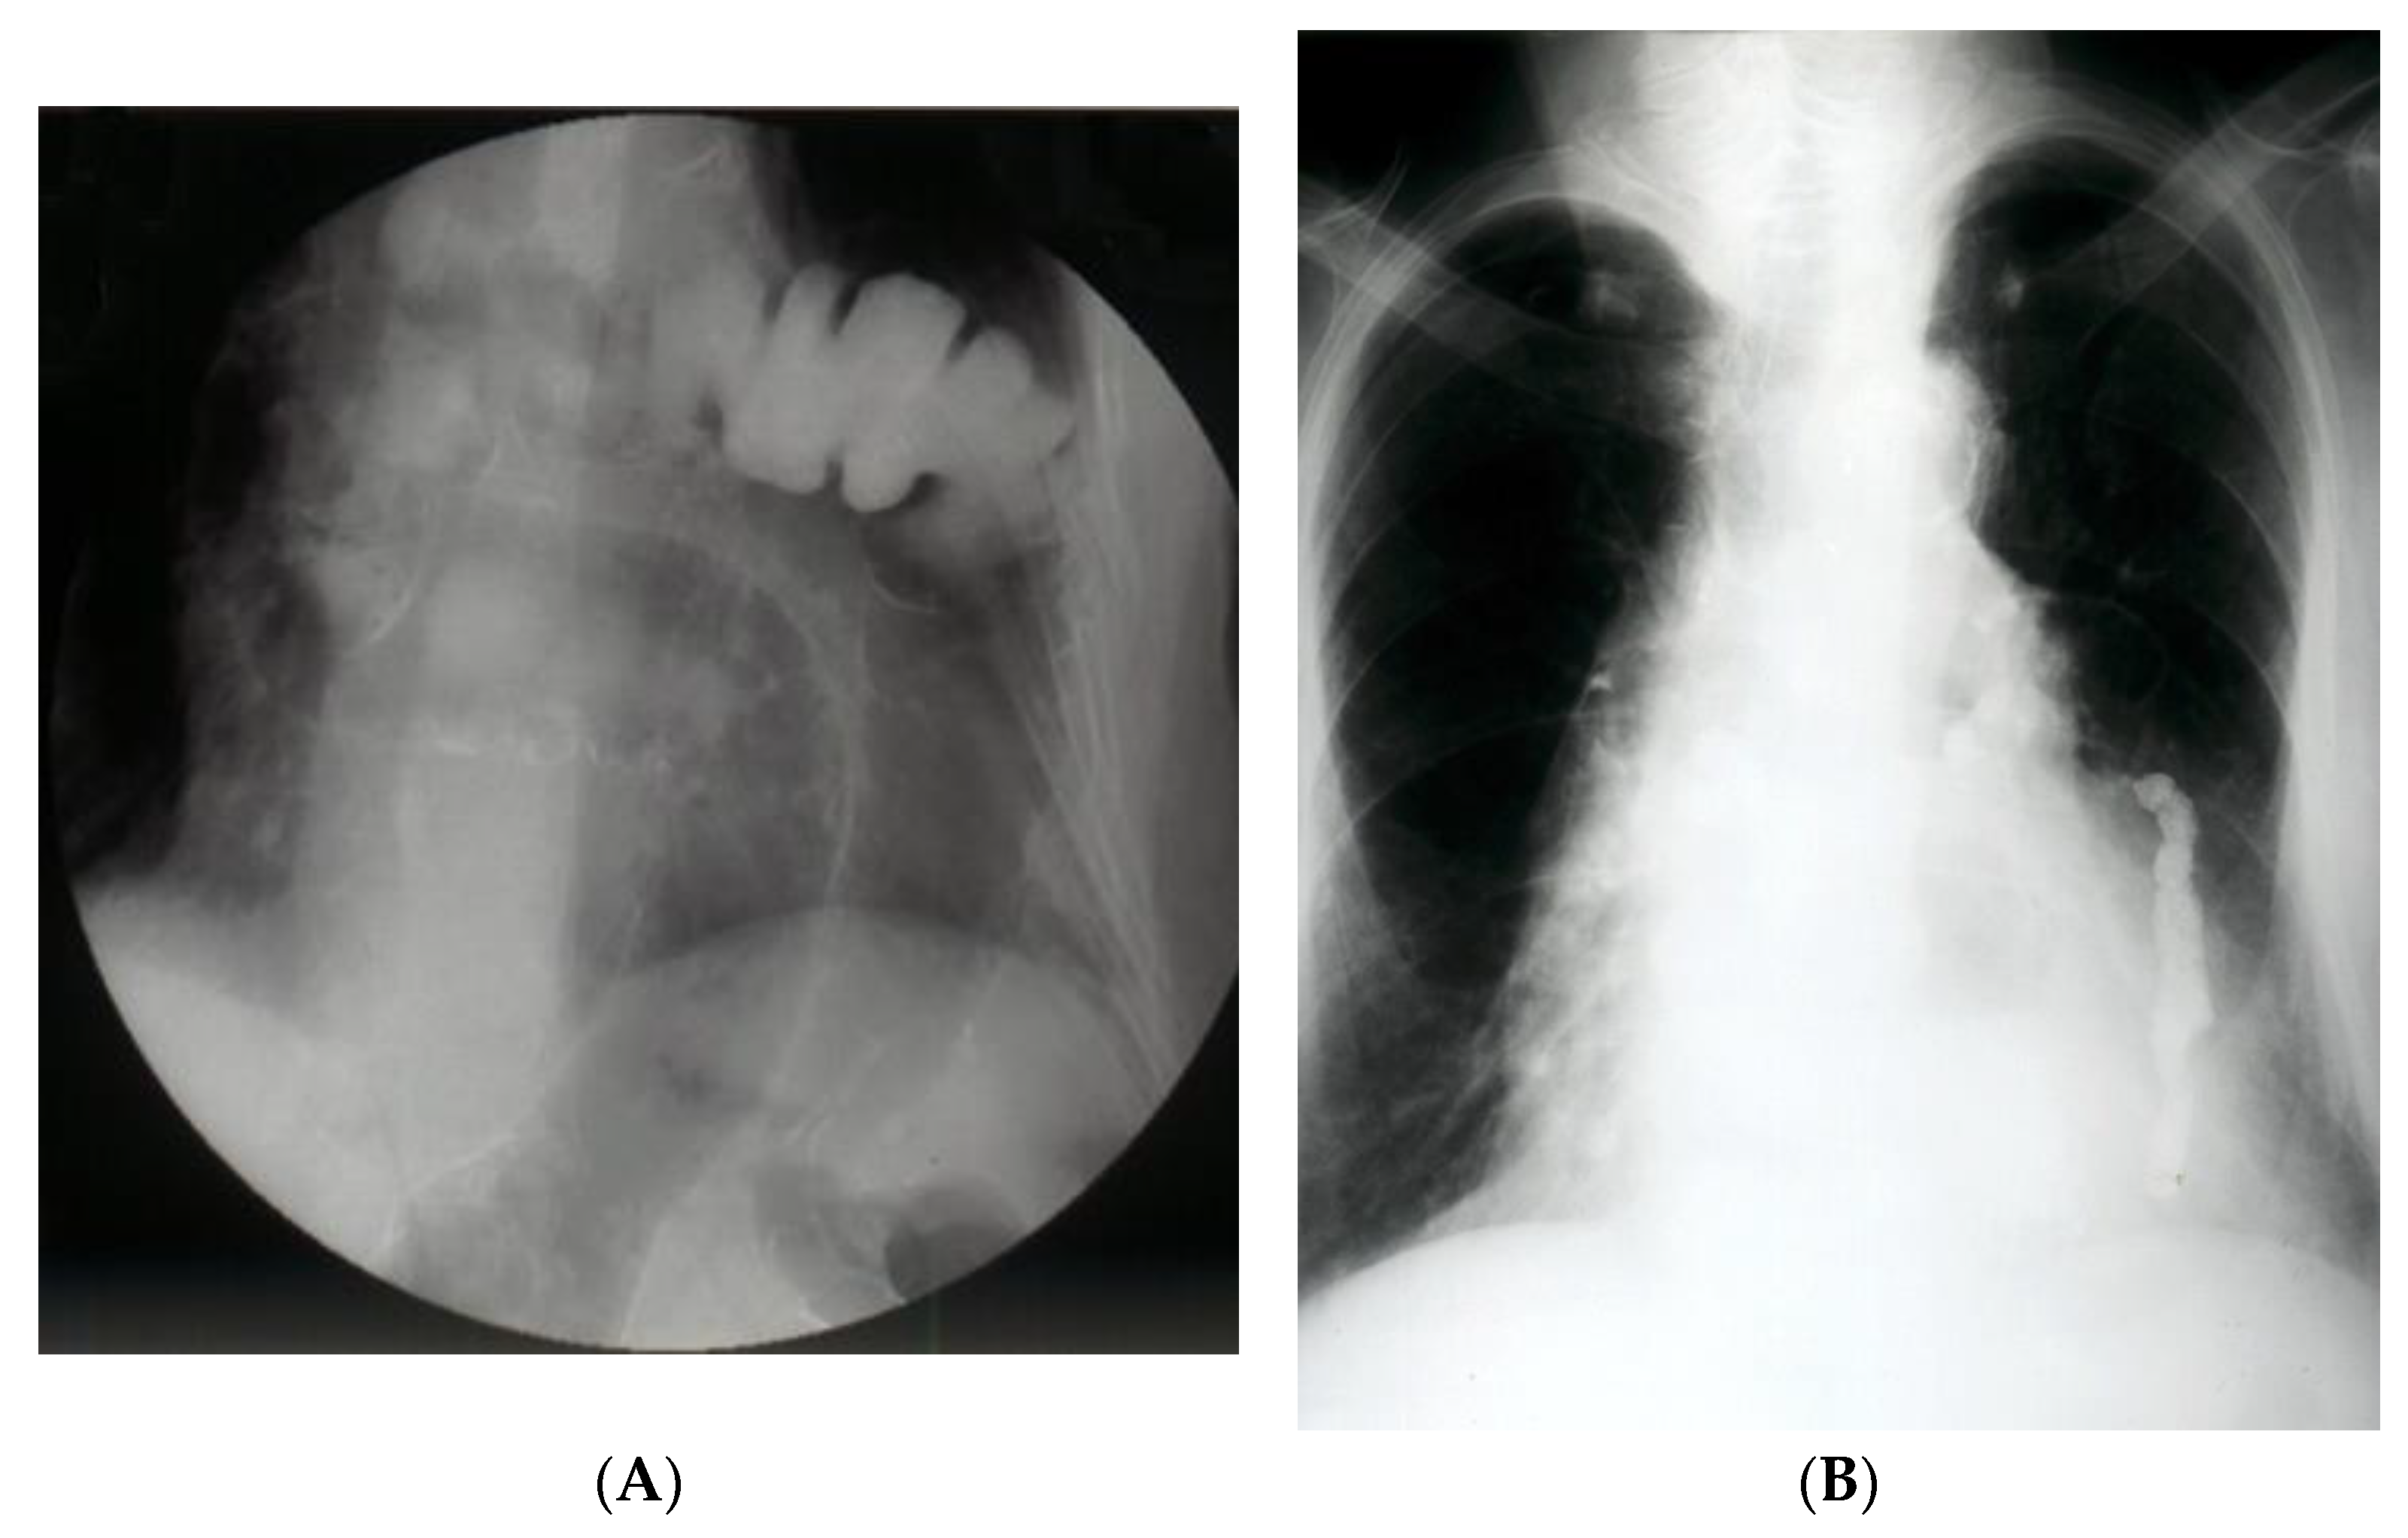

Chest X-ray is most often the first radiological investigation performed in these patients (90%). Chest and abdominal X-ray is recommended to be performed in multiple incidences, including the Trendelenburg position. Specific radiological signs are opacification of the lung bases, especially of the posterior fields depending on the contents of the hernial sac (Figure 1), intrathoracic localization of the abdominal viscera, and left hemidiaphragm elevation (more than 4 cm) with or without atelectasis. In general, diagnosis is more difficult when the hernial orifice is located on the right hemidiaphragm.

The contrasting exam has its advantages in allowing the identification of the digestive viscera by directly opacifying the herniated organ (Figure 2A,B). Furthermore, it can identify upside-down movements, highlighting fixation, incarceration, or even visceral strangulation.

Figure 1. Simple imaging assessment—radiography. The presence of the colon, ascended transdiaphragmatically through a Bochdalek hernia, at the level of the left hemithorax is noted.

Figure 2. (A). Contrast radiology—irrigography. The intrathoracic presence of the colon is noted through a Bochdalek hernia (A) or post-traumatic (anamnesis) hernia (B).